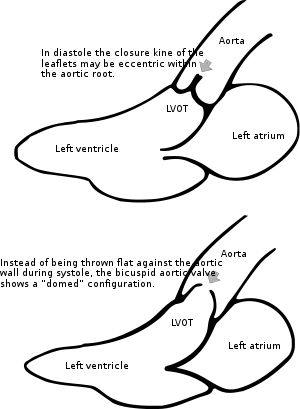

Bicuspid aortic valves may assume three different types of configuration:[20]

- "Real" bicuspid valves with two symmetric leaflets

- A tricuspid architecture with a fusion of two leaflets

- A tricuspid architecture with a fusion of three leaflets